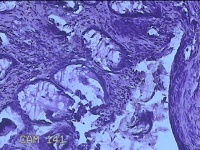

性别

男

年龄

40岁

临床诊断

混合痔

一般病史

反复肛门肿物突出15年。

标本名称

肛门肿物

大体所见

灰白暗红色肿物0.7x0.5x0.2cm一个,表面糜烂。

脱水、透明,浸蜡、脱蜡效果不佳,制片质量差。